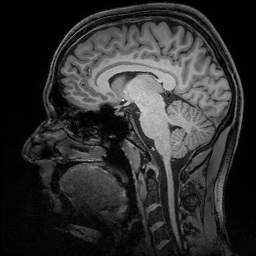

La risonanza magnetica fornisce informazioni sul cervello. (Fonte: DZNE / Guido Hennes)

Il team è riuscito ad individuare questa posizione fino a circuiti specifici nel cervello umano, usando un tipo particolarmente accurato di tecnologia di risonanza magnetica (MRI). I ricercatori auspicano che i risultati e il metodo del loro studio possano aiutare a capire meglio gli effetti dell'Alzheimer sul cervello. La ricerca è stata pubblicata sulla rivista scientifica Nature Communications.

Per questo studio, gli scienziati hanno esaminato il cervello di persone che si erano offerte di partecipare ad un test della memoria. I ricercatori hanno usato un particolare tipo di tecnologia di risonanza magnetica chiamato «7 Tesla ultra-high field MRI» che ha consentito di determinare l'attività in specifiche regioni cerebrali con una precisione senza precedenti.